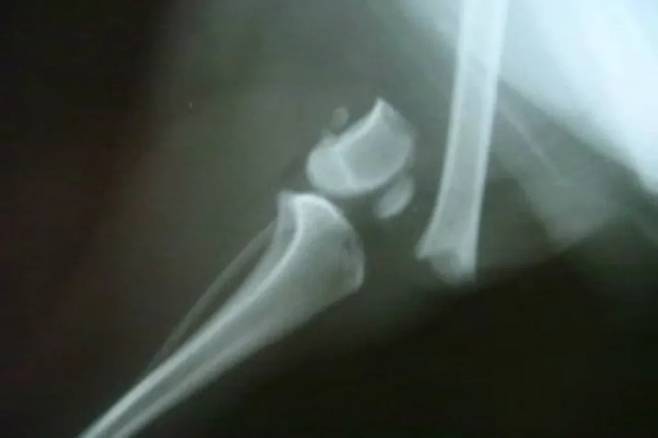

일상 동작으로 뼈가 부서진다면?

기침하거나 움직임만으로도 뼈가 금이 가거나 부러진다면 이는 비정상적입니다.

이 현상은 골암으로 인해 뼈의 구조가 약해져 작은 충격에도 손상되는 상태를 나타냅니다. 병적 골절은 극심한 통증을 유발하며 일상생활에 큰 제약을 줍니다.